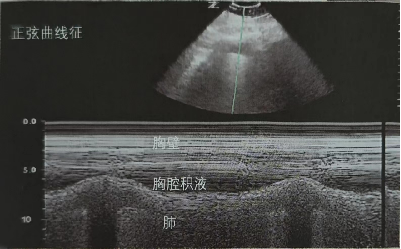

3. 胸腔积液

在二维超声图像中可看到“四边征”视频4,胸腔积液的四周由胸膜线(上界),肺(下界),两侧的肋骨影构成。M型超声下观察正弦曲线征图8,正弦曲线征表示浮动的肺随着呼吸朝向胸壁的运动,是胸腔积液的特征性表现。

图片

图8  正弦曲线征